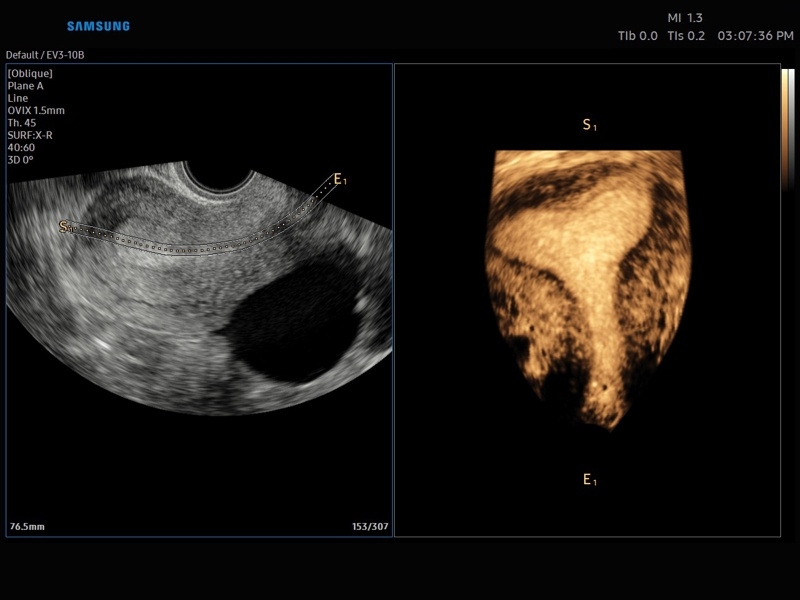

• Smart 4D с технологиями Realistic VUE и Crystal VUE

• Акушерство и гинекология

• 3D - трехмерное сканирование объемными датчиками в статическом режиме в серой шкале и восстановление объемной структуры сосудов в режиме цветного / энергетического допплера (необходим Static 3D).

• 4D - трехмерное сканирование объемными датчиками в реальном масштабе времени (необходима опция Smart 4D).

• Модуль Realistic Vue - программа реконструкции реалистичного 3D УЗИ, при котором на объемное изображение накладывается виртуальный источник освещения. Специальный процессинговый алгоритм воспроизводит трехмерную анатомию плода с исключительной детализацией.

• МодульCrystal Vue- программа реконструкции прозрачного 3D УЗИ, которое получается при одновременном усилении внутренних и наружных структур. Применяется для визуальной оценки состояния плода и матки, помогает лучше идентифицировать мягкие ткани и кости.

• Система Static 3D - трехмерное сканирование объемными датчиками в статическом режиме в серой шкале и восстановление объемной структуры сосудов в режиме цветного / энергетического допплера).

• СистемаLive 3D- трехмерное сканирование объемными датчиками в реальном масштабе времени (4D).

• MSV(Multi-Slice View илимультислайсинг) - возможность одновременного просмотра на экране множественных срезов, полученных при трехмерном сканировании.

• VolumeCT - трехмерная реконструкция изображений в виде куба (Cube Sectional View) или трех пересекающихся плоскостей (Cross View).

• OVIX(Oblique View eXtended) - получение фрагмента трехмерного изображения (в виде нескольких полупрозрачных сканов, последовательно наложенных один на другой) в направлении произвольного косого среза трехмерного объекта исследования.